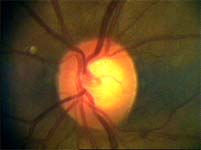

Tento terč má širokou cirkulární peripapilární atrofii, která opticky vytváří falešný dojem širokého neuroretinálního lemu, zvláště nasálně.

Na kterém oku je exkavace větší, na pravém nebo na levém? Podle pohledu na fotografie jistě na levém.

exkavace pravé oko

Na kterém oku je exkavace větší, na pravém nebo na levém? Podle pohledu na fotografie jistě na levém.

Co je příčinou toho, že při pohledu na snímky hodnotíme rozsah exkavace nesprávně? Je to skutečnost, že i růžová oblast neuroretinálního lemu může být již prohloubená, což vídáme zvláště na počátku rozvoje glaukomové neuropathie.

A jak se můžeme vyhnout záměně okrsku bledší barvy za skutečnou exkavaci? Tím, že budeme mít na paměti, že exkavace může být větší než nablednutí. Také zařazení zeleného filtru na pomůže snížit nežádoucí barevný kontrast.

Cévy

Jaké informace nám mohou říci cévy o poškození terče glaukomem? Cévy kopírují povrch terče, jeho nerovnosti se projevují záhyby cév. Při glaukomu mohou být obnaženy cévy, které dříve probíhaly v n. lemu. Při pokročilého glaukomu se zužují arterie a vzniká arteriovenózní nepoměr!

Na dolním pólu terče je patrný zálom vény, která zviditelňuje přítomnost i hloubku exkavace až k dolnímu okraji terče.

V nasálním horním kvadrantu terče vidíme obnažené cévy, které dříve probíhaly v lemu. Toto obnažení může být jedním z prvních příznaků glaukomové neuropathie.